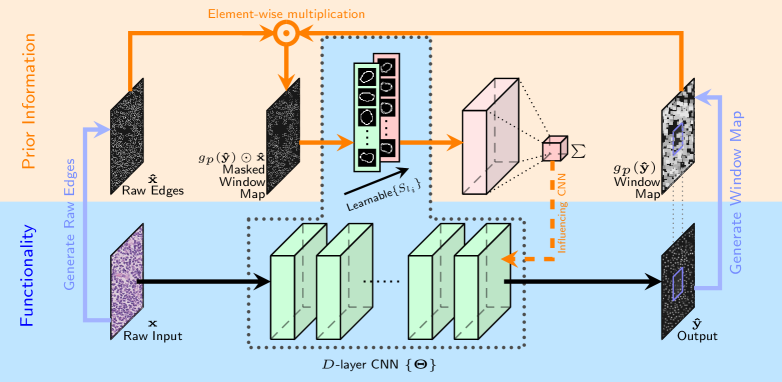

While exploiting a shape set provided by a domain expert is meritorious, a fundamental open question is: What is the best, most compact shape set to employ and can it be adapted based on the image characteristics? This section provides an answer to that question in the following manner: the set of shapes can be seen as a collection of filters, which we now add to the network as a learnable component and call it the learnable shape layer – see Fig. 4 for an illustration of this idea. We call this new network structure as Tunable Shape Priors with CNNs (TSP-CNN).

We observe that the domain expert provided shape set in practice is quite redundant, i.e. it may contain pairs of hand-crafted shapes that are quite close to each other and do not add value to nucleus detection. We therefore propose a two stage process to arrive at a compact Basis Shape Set which is adapted based on training imagery: 1.) shape elimination stage to obtain a reduced/smaller reference shape set, and 2.) shape refinement or learning via TSP-CNN. This two stage process is illustrated in Fig. 5. For both stages, meaningful shape similarity measures are needed; the exact shape elimination and refinement procedure is detailed next. We next introduce shape elimination and refinement procedures, and then describe the training procedure to learn shapes that are adapted to the underlying dataset.